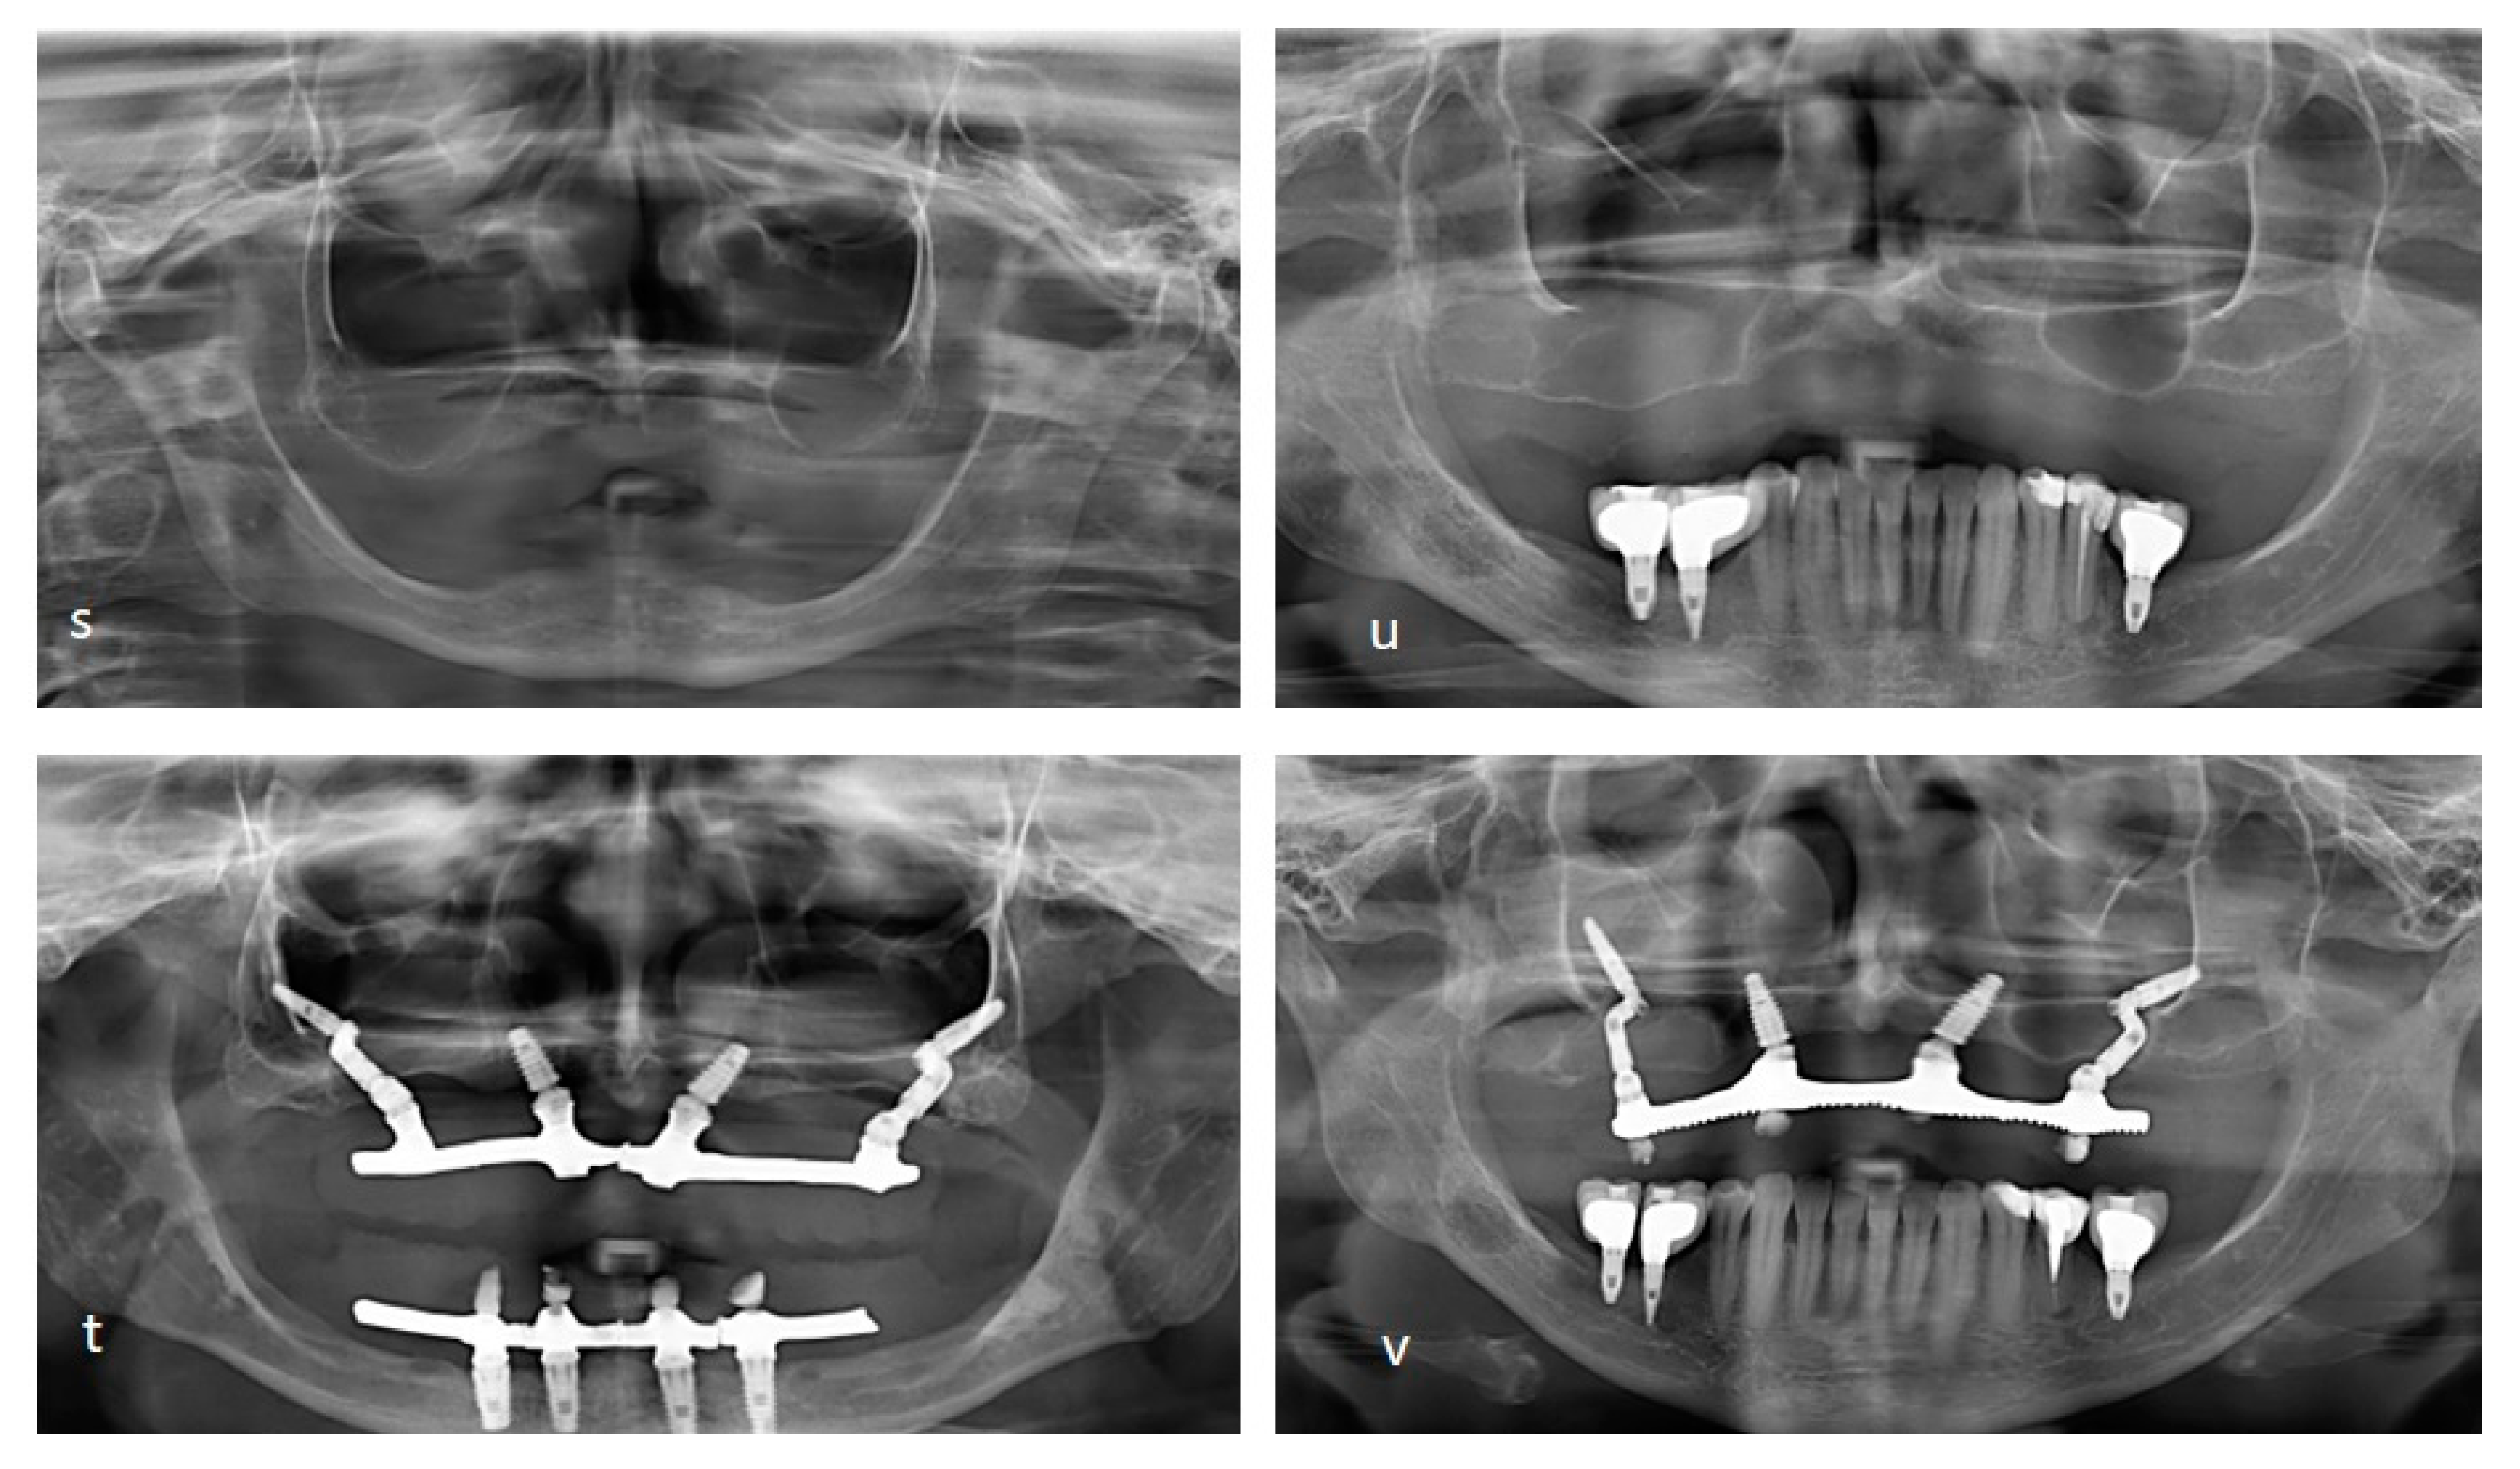

Figure 8.

The initial condition, monitoring by 26 months after the surgical of a male patient, at 66 years (s-t) and a female patient at 60 years with monitoring by 36 month (u-v). It is possible to use the Facco technique with different angles between the zygomatic bone and the lateral wall of the maxilla. Based on the classification for zygomatic implant patient based on the zygoma anatomy guided approach [

3], type 0 and 1 can be performed through a groove to access the maxillary sinus and move it. It is possible to achieve better anchorage using a more favorable angle for this maneuver compared to the traditional zygomatic implant technique. For type 2, the Pilar Z makes it possible to move the sinus wall slightly to insert the implant in the closest ideal position. Access to the sinus wall is not necessary for types 3 and 4. With all these adaptations provided by using the Pilar Z, it is possible to reduce and avoid post-surgical complications resulting from installing an implant in the zygomatic bone, as well as rhinitis and sinusitis, difficulty and discomfort when using the prostheses, the appearance of implant threads and perio-implant problems resulting from tissue recession, or musosites. These gains are mainly possible due to part C of the component, which is thinner than traditional zygomatic implants and is positioned with at least half of its length inside the bone, allowing better adaptation in the wider region of the zygomatic bone (approximately 4.1mm) [

4].